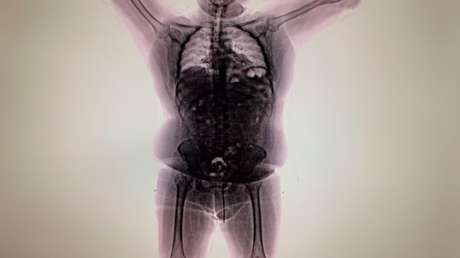

Sin embargo, su plan quedó frustrado cuando la Policía de Seguridad Aeroportuaria de Ezeiza detectó en él un comportamiento extraño y procedió a revisarlo con un escáner corporal, lo que permitió descubrir que tenía los intestinos repletos de dedales de cocaína.

Tras el arresto, Morales pidió atención médica inmediata y dijo que tenía problemas de salud, entre ellos una hernia discal, niveles elevados de colesterol e hígado graso. La policía lo internó en el Hospital de Ezeiza, bajo custodia, y allí expulsó todas las cápsulas que había ingerido y que finalmente dieron positivo para cocaína.